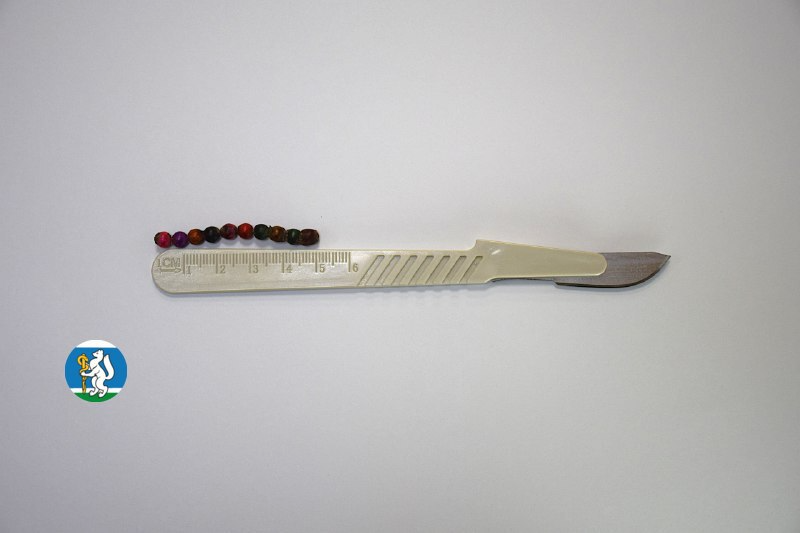

«Для минимизации риска осложнений удаление инородных тел было проведено интраоперационно. В ходе вмешательства дежурная бригада врачей извлекла 10 магнитных шариков, цепочка которых в длину составила 5 сантиметров», — рассказал детский хирург ДГКБ №9 Андрей Чукреев.